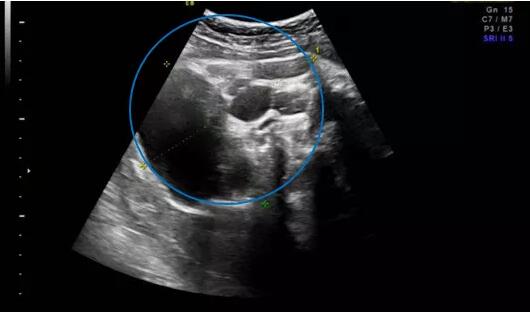

几个月前,家住外地的准妈妈唐女士(化名)在当地医院产检时,超声发现肚里的宝宝患有骶尾部畸胎瘤,直径达5厘米,近乎胎儿头颅大小,当地医院建议终止妊娠。“二胎放开以来,我和我老公就一直想再要个孩子,好不容易怀上了,我们真舍不得。”唐女士说道。抱着试试看的想法,唐女士被转诊到青岛妇儿医院胎儿医学门诊。

在听到专家们专业全面的咨询后,唐女士决定积极配合治疗。后期体检中,宝宝的畸胎瘤逐渐增长,分娩前最后一次超声提示畸胎瘤直径达10cm,但并未出现羊水过多等异常情况。